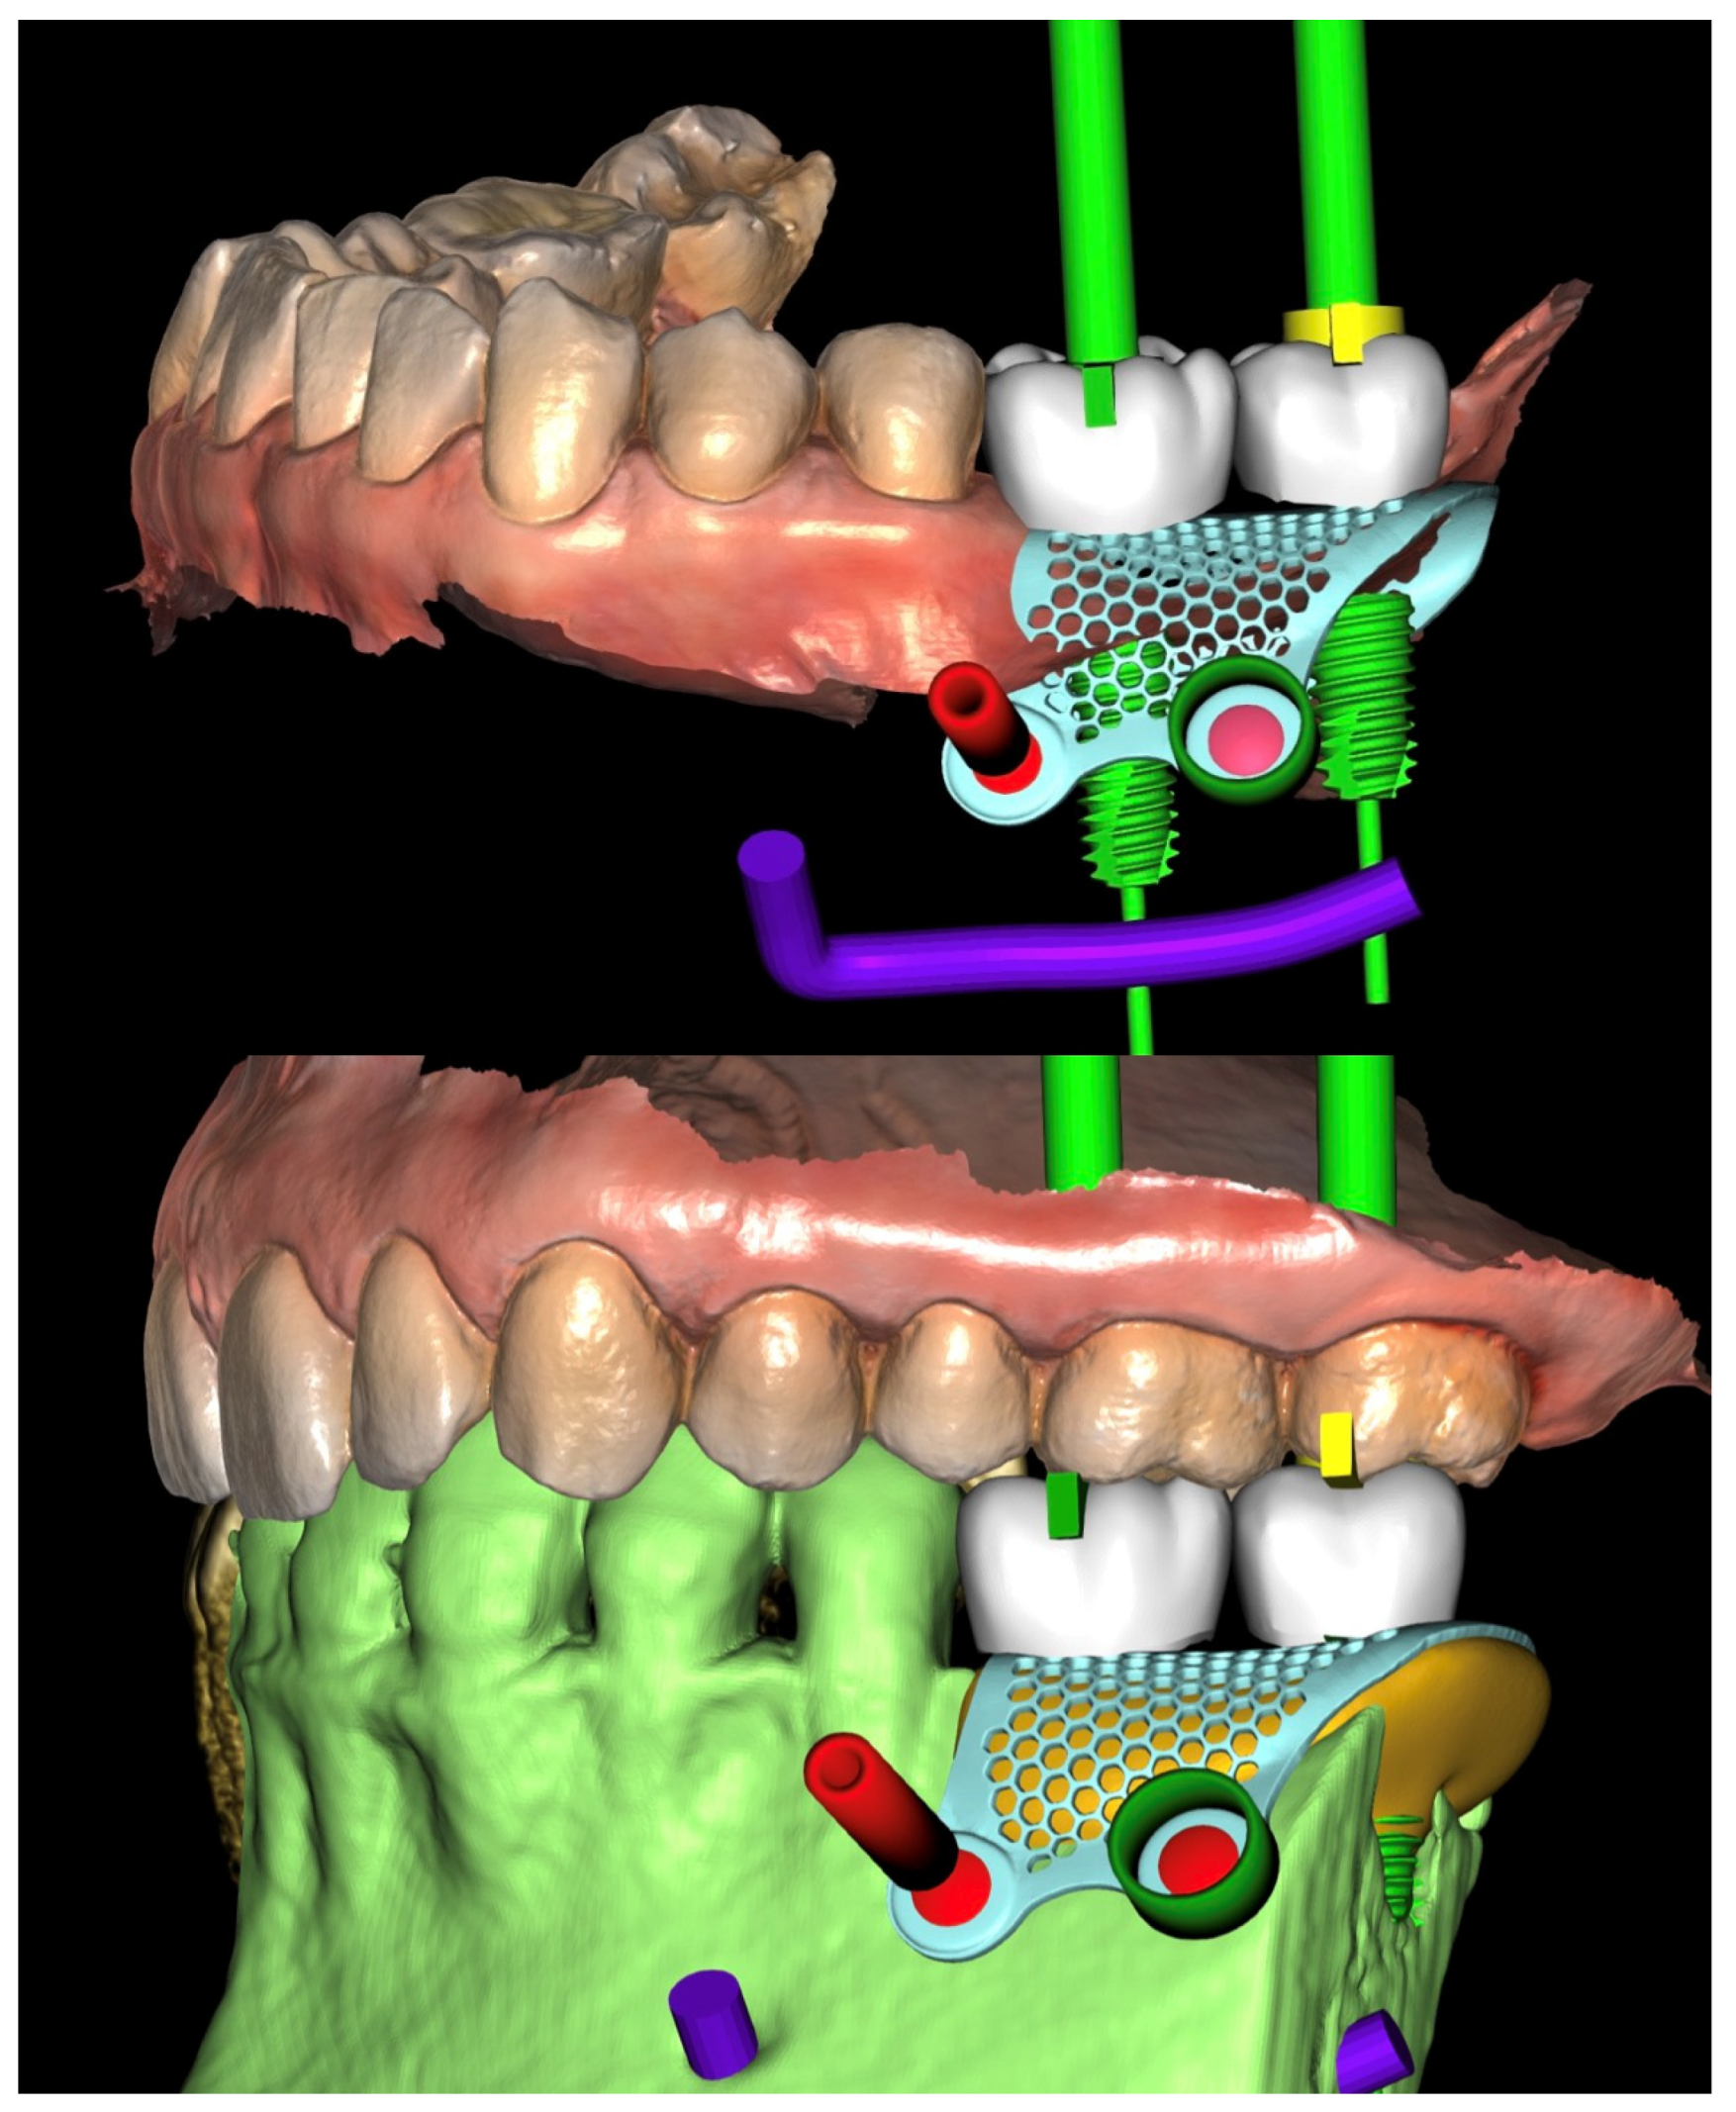

2. Case Summary